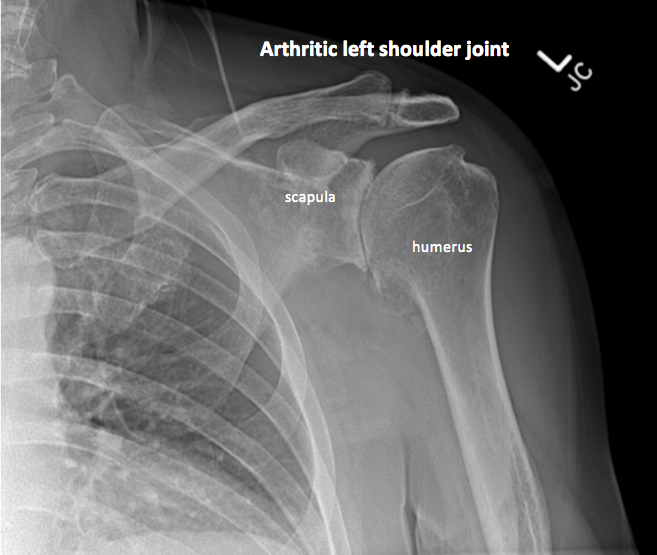

Рентген плеча: примеры снимков и их расшифровка